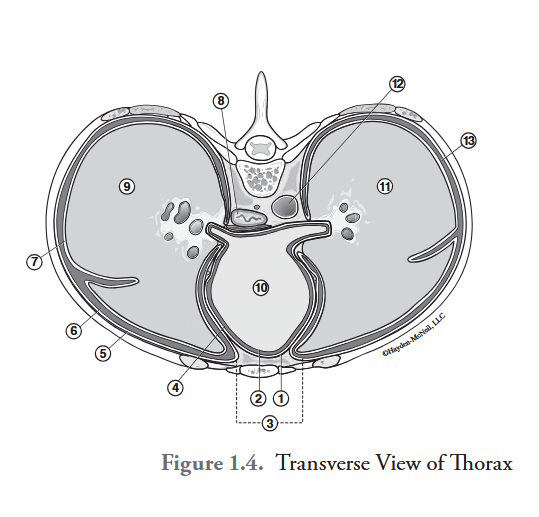

What is labeled #1?

parietal pericardium

What is labeled #2?

visceral pericardium (epicardium)

What is labeled #3?

mediastinum

What is labeled #4?

pericardial cavity

What is labeled #5?

parietal pleura

What is labeled #6?

right pleural cavity

What is labeled #7?

visceral pleura

What is labeled #8?

esophagus

What is labeled #9?

right lung

What is labeled #10?

heart

What is labeled #11?

left lung

What is labeled #12?

descending aorta

What is labeled #13?

left pleural cavity